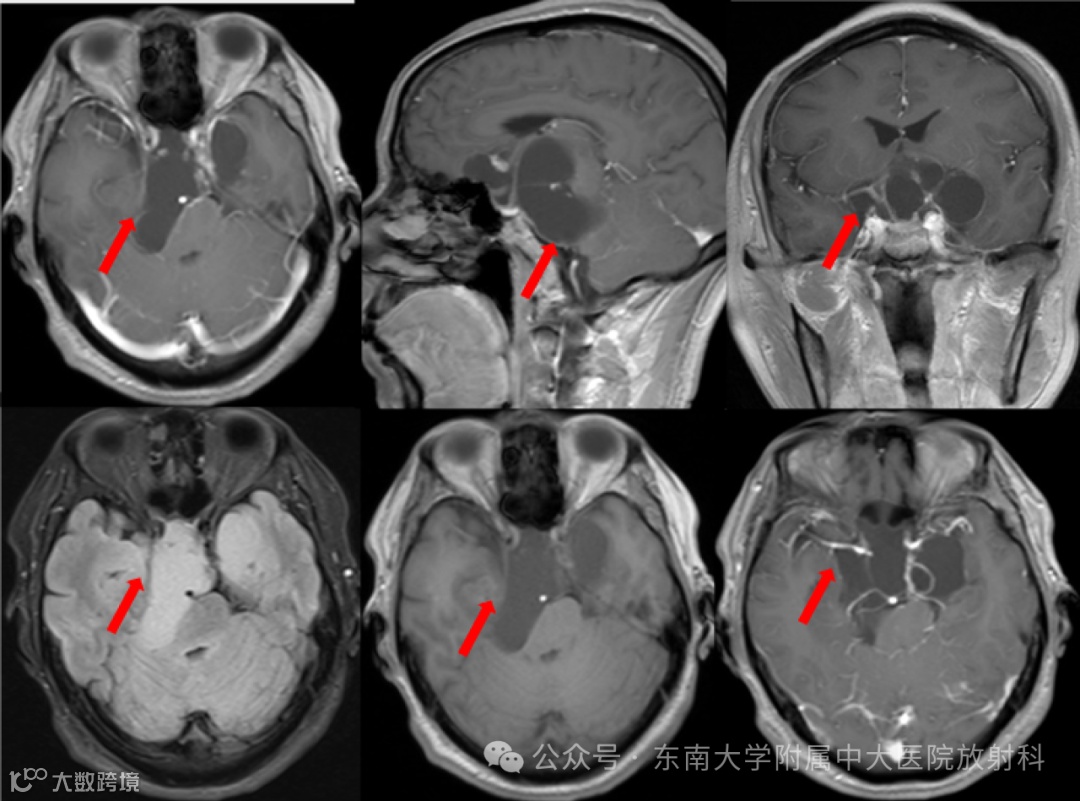

患者,男,57岁

主诉:右面部麻木伴记忆减退10月余,发现鞍区占位10月

现病史:患者 10 月余前无明显诱因出现右侧面部麻木感,伴有记忆力减退情况,至当地医院检查示鞍区占位,定期复查,未予特殊处理。双眼视物模糊,左侧较明显,无发热寒战,无言语功能障碍,无肢体感觉异常,无心慌胸闷,无腹痛腹胀。现患者为求进一步诊治至我院就诊,门诊拟“鞍区良性肿瘤”收住入院

影像学表现